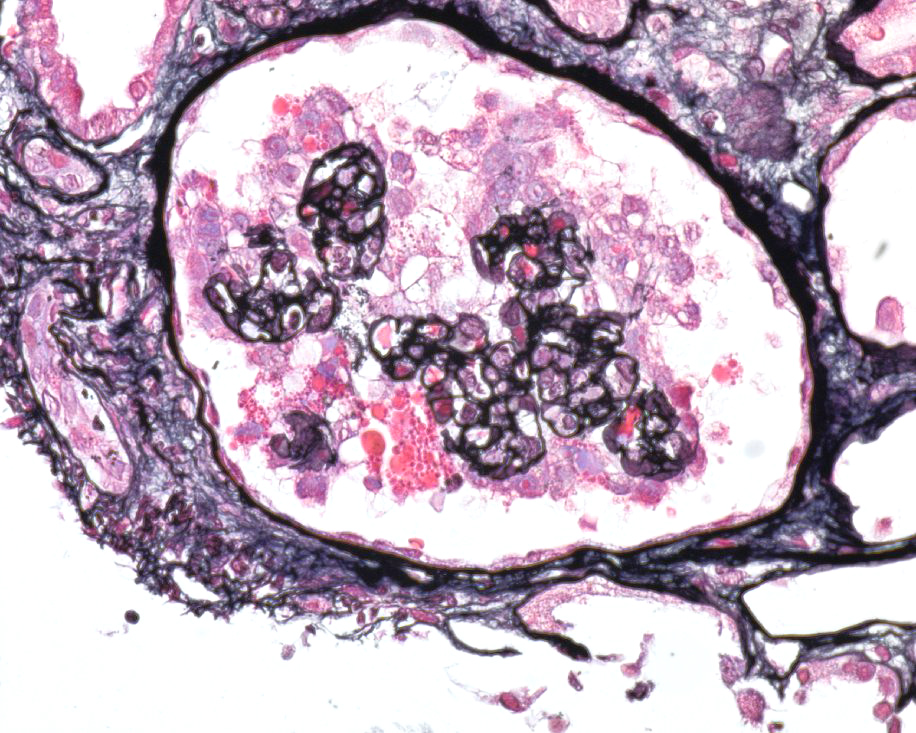

How about our patient with COVID-19 and nephrotic syndrome? The biopsy reveals collapsing FSGS!

Above, we see collapse of the capillary loops along with hypertrophy and hyperplasia of the podocytes. We also see effaced podocytes under electron microscopy (EM). Viruses have been commonly associated with collapsing FSGS or collapsing glomerulopathy (think: human immunodeficiency virus (HIV), cytomegalovirus (CMV), parvovirus B19) – and seem SARS-CoV2 has been added to the list: meet COVAN (COVID-19 associated nephropathy). Collapsing glomerulopathy has been reported in individuals of African ancestry with COVID-19 and high-risk apolipoprotein 1 (APOL1) alleles. A proposed pathogenesis of COVAN is summarized in the figure below.